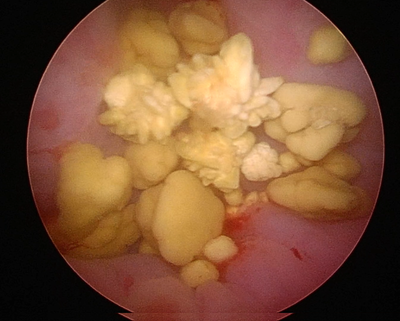

膀胱鏡で見た結石

一方で表面に多くの突起があるようなストルバイト結石などもあります。このような場合にはこの棘が膀胱粘膜を傷つけてしまい、血尿や排尿痛などの症状が強く出ます。

犬の膀胱鏡で見た膀胱結石

棘が多く形成されたストルバイト結石